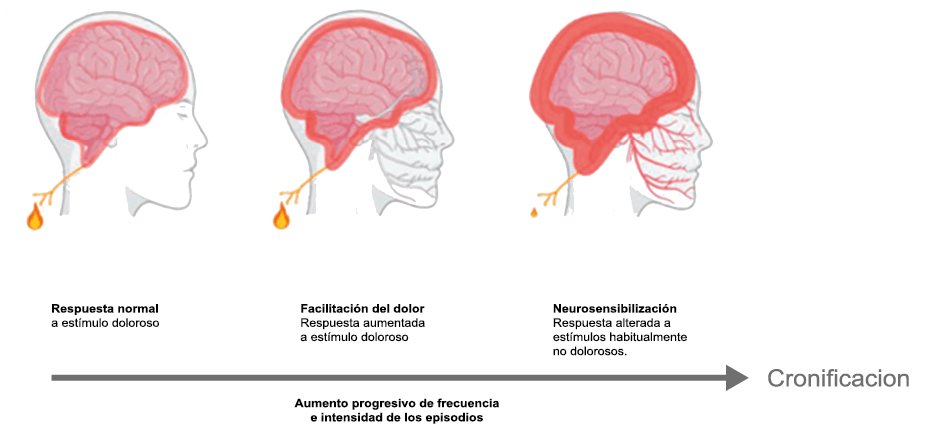

Hoy en día, la migraña se describe más comúnmente como un “trastorno neurovascular” y específicamente como un trastorno del cerebro. Una teoría que ha cobrado importancia en los últimos 15 años, que sostiene este punto de vista y ha servido para explicar muchas características de la migraña que antes no se habían explorado o simplemente no estaban claras es la “sensibilización periférica y central”. La sensibilización es una característica común de muchos trastornos de dolor crónico y se supone que también está presente durante la migraña. Es una activación y sensibilización de larga duración de los nociceptores periféricos y las neuronas nociceptivas centrales y puede explicar la longevidad del ataque de migraña y la transición hacia la migraña crónica, así como síntomas relacionados específicos(96). La sensibilización central de las neuronas trigeminovasculares ha ayudado a nuestra comprensión de la base neural de la hipersensibilidad extracraneal en la migraña, la derivación del dolor y la alodinia a las áreas faciales periorbitarias y cutáneas(97). Es probable que la sensibilización de las neuronas trigeminotalámicas explique la alodinia cutánea generalizada en las regiones extracefálicas(98).

Un principio importante de esta teoría es que el desencadenante principal de la migraña proviene de la periferia, en los vasos sanguíneos de la duramadre, con la activación del sistema trigeminovascular proveniente del disparo de las neuronas trigeminales periféricas de primer orden en respuesta a una lesión nociceptiva o señales provenientes de las meninges que liberan mediadores neuroinflamatorios. La activación sostenida de las neuronas nociceptivas meníngeas durales provoca la activación secuencial y la sensibilización de las neuronas trigeminovasculares de primer orden (nociceptores periféricos), segundo orden (a nivel del TCC-complejo trigémino cervical) y tercer orden (trigeminotalámico), (Figura 5) así como la activación ascendente del cerebro, tallo y otras estructuras diencefálicas(97).

Se cree que esta activación secuencial explica la naturaleza pulsátil del dolor en la migraña, la hipersensibilidad sensorial nociceptiva, los síntomas neurológicos asociados que incluyen náuseas, vómitos, alteración de la alimentación y el sueño, así como la alteración cognitiva. Clínicamente, sin embargo, hay muchas lagunas. Los síntomas premonitorios en la migraña pueden estar presentes 24 a 48 h antes del dolor de cabeza y están representados por cambios en la activación en las regiones del cerebro medio e hipotalámico. Los desencadenantes de la migraña, como la privación de sueño y alimentos y el estrés, están bajo control homeostático.